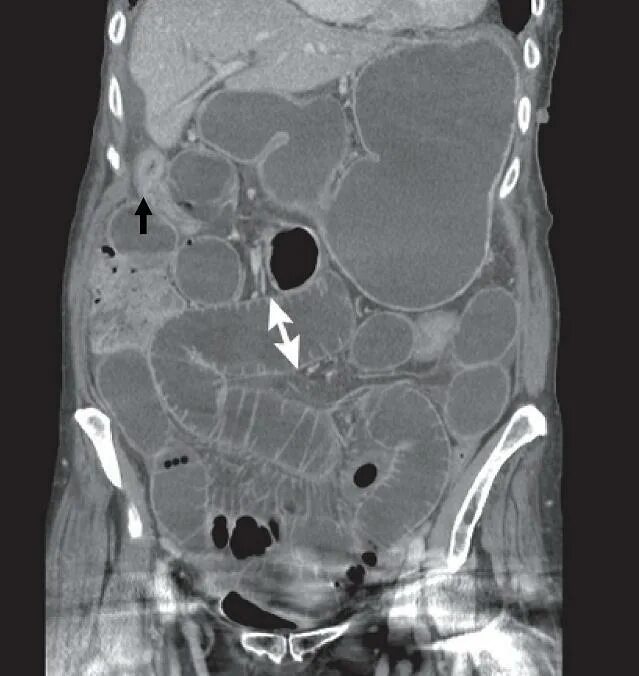

Обследование кт кишечника